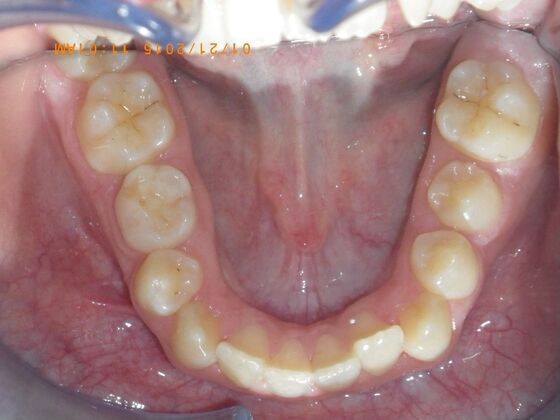

Orthodontics: Case 10

Description

This case presents with a dental midline discrepancy. The upper incisors are tipped toward the palate, which prevents the lower incisors from establishing proper arch form. The upper right molar has drifted forward, causing the upper midline to be skewed to her left. By distalizing the upper left molar, we can correct the midline discrepancy. Lastly, both upper and lower arches need expansion. All of this was completed with conventional straight wire appliances within 2 years.